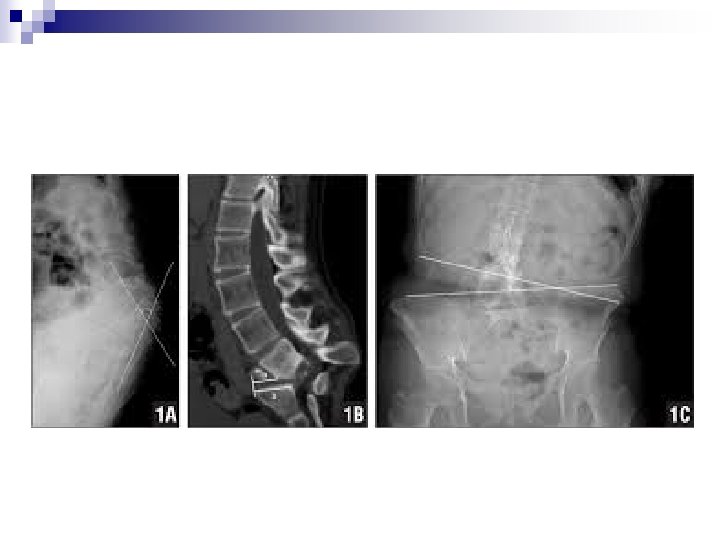

n Bassin : Le déséquilibre du bassin sera mesuré au niveau des têtes fémorales. En dessous d’un cm l’inégalité de longueur des membres inférieurs est physiologique. Le bassin se comporte souvent comme une courbure de compensation de la scoliose. On l’appelle la vertèbre pelvienne. Au delà de 2 cm une compensation par talonnette est indispensable.

L'inégalité de longueur des membres inférieurs est un problème de pratique quotidienne. Quelques règles sont à connaître. - Pas de correction en dessous de 10 mm d'inégalité - Correction systématique au delà de 20 mm - En cas de scoliose, on évitera une modification de la posture durant la période de croissance pubertaire, - En cas de doute on réalisera deux mesures de la gibbosité. L'une sans compensation et l'autre avec compensation. On corrigera si la compensation améliore la gibbosité. - En fin de croissance, seule la persistance d'un déséquilibre de l'axe occipital justifie une compensation. La bonne triade est : - Inégalité entre 10 et 20 mm - Amélioration de la gibbosité avec la talonnette